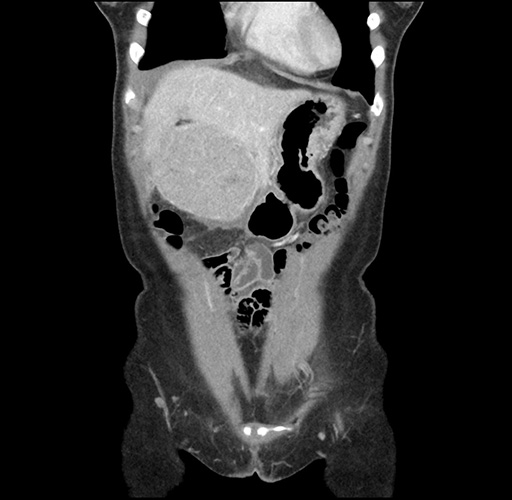

Imaging Analysis

Look through the patient's CT scan to identify any areas of concern for the necessary procedure.

Based on your CT findings, which issue(s) would give reason for "planned slowing down moment(s)" in this case?